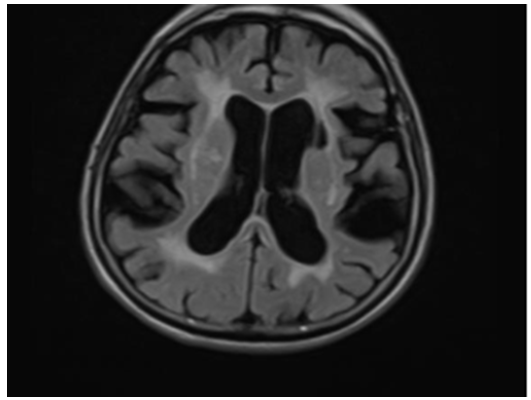

A 76-year-old woman with known hypertension, diabetes mellitus, hypothyroidism was admitted with complaints of increased forgetfulness, urinary incontinence and impaired balance for about 6 years. She was hospitalized with the preliminary diagnosis of Normal Pressure Hydrocephalus (NPH) because of the expansion of periventricular distances in radiological imaging. She was conscious and oriented but had limited cooperation. There was no sign of meningeal irritation and no nuchal rigidity. Her speech was fluent, and she had a complete understanding. Cranial nerve examination was normal. Motor system examination revealed bilateral shoulder muscle strength 3/5, elbow muscle strength 4/5 and wrist muscle strength 5/5. In other words, the patient had proximal dominant muscle weakness on the upper and lower and the appearance of the MIBS. Deep tendon reflexes were normoactive bilaterally; Hoffman sign was positive bilaterally; abdominal skin and jaw reflex were normal. The sensory system examination revealed a superficial sensory defect on the soles of the feet, the cortical sensation was normal, deep sensation in the lower extremity was decreased. Extrapyramidal and autonomic system examination was normal. The cerebellar examination was consistent with motor weakness. She had no ataxia and was spinning in 3-4 steps. Standardized mini-mental test was 22 points out of 30. The CSF dynamic MRI was consistent with small vascular disease and advanced encephalomalacia (Figure 1). On cervical MRI, C4-C5 and D4-D5 vertebrae were fusion with each other, and protrusions accompanied by dorsal osteophytes, spinal cord compression and accompanying myelomalacia were observed in C5-6 and C6-7 (Figure 2). Dementia had been attributed to chronic vascular disease. The current neurological deficit, persistent gait and balance disorder, loss of fine motor skills and bladder dysfunction were thought to be due to advanced cervical stenosis. An elective cervical laminectomy was planned, but it could not be performed due to additional comorbidities. Conservative therapy was suggested. Physical therapy was planned to preserve a range of motion of the upper extremities. Replacement therapy was given for vitamin d deficiency.

Figure 1:The CSF dynamic MRI showing small vascular disease and encephalomalacia.